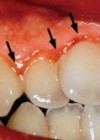

Aplikums satur miljoniem baktēriju, jo siltais un mitrais mutes dobums ir ideāla vide, lai baktērijas vairotos. Barībā esošais cukurs reaģē ar baktērijām, veidojot skābes, kas postoši iedarbojas uz zoba audiem un smaganām. Ja aplikumu ilgstoši nenoņem, tas sāk mineralizēties, un veidojas zobakmens. Smaganas pakāpeniski atkāpjas, veidojot smaganu kabatas, zobi kļūst kustīgi.

Bērniem līdz 18 gadu vecumam zobu higiēnista pakalpojumu izmaksas sedz veselības norēķinu centrs. Viņiem nāk par labu zobu pulēšana, fluora gēlu un citu fluoru saturošu preparātu uzklāšana, kas novērš zobu bojāšanos. Drošs un nesāpīgs veids, kā aizsargāt bērna zobus no bojāšanās, ir silanti. Pārklājot ar tiem sānzobu kožamo virsmu, mēs tos pasargājam no barības atliekām un mikrobu vairošanās, kas savukārt izraisa zobu bojāšanos. Silantus vajadzētu likt bērniem uz viņu patstāvīgajiem zobiem, tiklīdz tie izšķīlušies, vai tuvāko sešu mēnešu laikā. Pirmos silantus uzklāj vecumā starp 6 un 7 gadiem. Pārējos starp 11-14 gadiem.